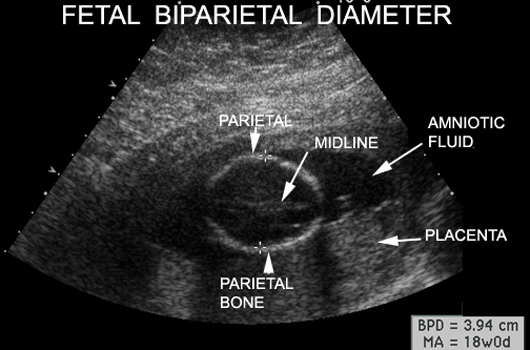

Effective uses of the FL/BPD ratio include its use as a quality control check on femur length and BPD measurements and its use to diagnose short-limbed dwarfism, hydrocephalus, and microcephaly . Pregnancy dating by means of BPD can now be cross checked by use of femur measurements and new Observations on normal and abnormal fetal growth will now be possible .

Fetal Dating , Biparietal Diameter, Femur Length , Portable Ultrasound Machine, Automatic Measurement 1 . Introduction . Ultrasound scanning in pregnancy has become the standard for care in the high income countries (HIC) [1] . It is currently offered at week 12 or around week 18, or both .